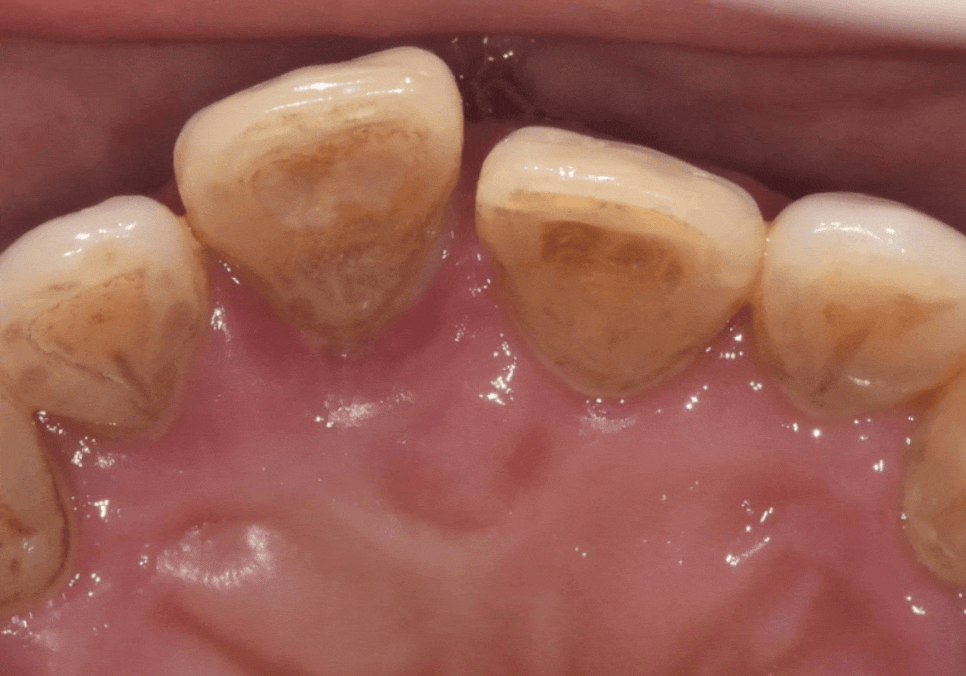

이 정도의 염증이라면 양옆에 치아도

안전할 수 없는 상황...

아니나 다를까.

양옆의 치아들도 조금씩 흔들림이 진행되고 있었습니다.ㅜㅜ

앞니 길어짐, 위 앞니가 점점 내려온다면? '이것' 의심해 봐야 합니다.

하지만 양옆 치아들은 가운데 앞니보다 뼈 상태가

비교적 나은 상황이라

이대로 뽑기에는 아쉬움이 따르더라고요~

그래서 잇몸치료를 같이 병행하며

최대한 치아를 살려 써보기로 했어요.

하지만 뿌리 끝까지

뼈가 녹아버린 가운데 앞니(#11)는

그대로 두면 주변 뼈까지 모두 녹일 수 있었기에,

안타깝지만 발치 후 임플란트를

진행하기로 결정했습니다.